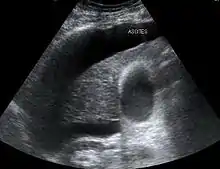

تعرف متلازمة الكبدية الكلوية حتى الآن، بأنها نوع من الفشل الكلوي الوظيفي في المرضى الذين يعانون من أمراض الكبد وارتفاع ضغط الدم البابي وتشكل ذروة التغيرات في الدورة الدموية الجهازية المرتبطة مع بوابة ارتفاع ضغط الدم. مع أنه في التشخيص تظهر الكلى سليمة شكليا، ولكن يكون هناك انخفاض في وظائف الكلى.[10] تنتج عن قصور كلوي تالٍ للقصور الكبدي في التشمع. تكون الكليتان طبيعيتين من حيث البنية الداخلية، ويعتقد أن القصور الكلوي ناجم عن اضطراب الجريان الدموي الجهازي بما في ذلك تدهور الجريان الدموي الكلوي. تحدث متلازمة الكبدية الكلوية في المراحل المتقدمة من التشمع المترافق دائمًاً مع الحبن، وهي تتميز بغياب البيلة البروتينية أو الرسابة البولية الشاذة، ويكون معدل إطراح الصوديوم البولي أقل من 10 ميلي مول في اليوم ونسبة أسمولالية البول على أسمولالية البلازما تزيد عن 1.5.من المهم أن ننفي نقص الحجم وذلك بقياس الضغط الوريدي المركزي وتسريب المحاليل الغروانية مثل محاليل الألبومين البشري للحفاظ عليه بحدود 0-5 سم ماء.[11] قد تتضاعف الآفة الكبدية الوخيمة مهما كان سببها بشكل خاص من القصور الكلوي الوظيفي ويطلق على هذه الحالة اسم المتلازمة الكبدية الكلوية. وتترافق هذه المتلازمة في كل الحالات تقريباً بوجود الحبن. تبقى الكليتان سويتين نسجياً في الحالات النموذجية وتحتفظان بقدرتهما على استعادة وظيفتهما تماماً في حالة شفاء الوظيفة الكبدية. يتميز الخلل الوظيفي الكلوي بنقص معدل الترشيح الكبي، وقلة البول، وانخفاض الصوديوم في البول ( أقل من 10 مك /ليتر )، والآزوتمية، وارتفاع نسبة آزوت اليورية الدموية إلى الكرياتينين.وتُعد متلازمة الكبد الكلوية، حالة مرضية خطيرة تهدد حياة الإنسان إذا أصيب بها. لكن الأسباب المباشرة للإصابة بها هو التدهور السريع في وظائف الكلى وإصابة الأفراد بتليف الكبد أو المداهم (فشل الكبد). على الرغم من العلاجات المختلفة لأعراض وأسباب هذه المتلازمة، مثل غسيل الكلى والعلاج بالأدوية، فإن الإصابة بالمتلازمة الكبدية الكلوية لها مضاعفات شديدة، عادة ما تكون قاتلة ما لم يتم تجرى عملية زرع للكبد، لأن أسباب حدوث هذا الشرط هي خلل في أجهزة حساسة ومهمة في جسم الإنسان؛ مثلاً يحدث الفشل الكلوي الحاد بسبب تليف الكبد وانخفاض مستوى وظائف الكلى وارتفاع ضغط الدم، ما يؤدي إلى تقليص إنتاج البول، نتيجة لانخفاض التخلص من البول وتغير لونه وتراكم النيتروجين في الدم. ويتميز هذا المرض بأعراض بدائية كاصفرار الجلد، زيادة في الوزن، انتفاخ البطن، تغيرات في الحالة النفسية، الخرف، التوتر، حركات لا إرادية، غثيان، تقيؤ. وتتطور هذه الأعراض ليحدث تليف الكبد، والتهاب الكبد الكحولي، وفشل كبدي حاد، والعدوى والنزيف المعوي، نقص ضغط الدم.